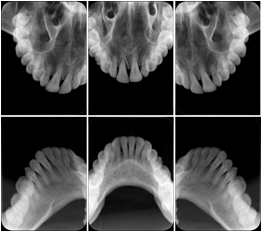

OO.1.2 Ophthalmology

1. A patient in rural Canada visits a general ophthalmologist and is found to have diabetic macular edema. The general ophthalmologist would like to discuss the case with a retina specialist before performing laser surgery. A fluorescein angiogram is done with multiple retinal images taken in a timed series after an intravenous injection. The images along with a Structured Display are shared via a Health Information Exchange with a retina specialist in Calgary, who opens them using his Ophthalmology EMR software and consults via phone with the general ophthalmologist. Both physicians view the images in the same layout so the retina specialist can provide accurate guidance for treating the patient.

2. A patient in rural Iowa visits his primary care physician for management of diabetes. Three non-mydriatic (patient's eyes are not dilated) photographs are taken of the back of each eye, and forwarded electronically along with a Structured Display to an ophthalmologist in Iowa City. The ophthalmologist reads the photos in an agreed upon layout so there is no mistake about what portion of which eye is being viewed. The ophthalmologist is able to tell the primary care physician that his patient does not need to come to Iowa City for face to face ophthalmologic care, but that there is a particular view of the left eye that should be photographed again in 6 months.

Ophthalmic Retinal Study Structured Display

Figure OO-3. Ophthalmic Retinal Study Structured Display